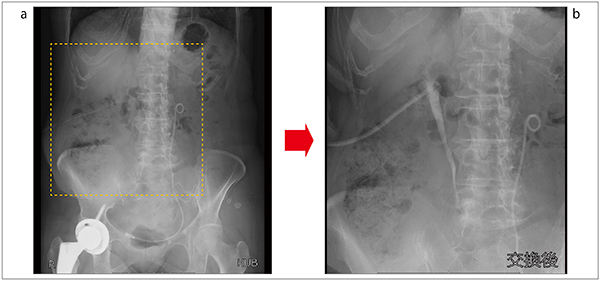

2.i-stitch

次に、“i-stitch”(長尺撮影)について紹介する。i-stitchは一連の曝射で全長撮影する機能で、主な使用目的は整形分野の全脊椎や下肢全長撮影である。当院では一般撮影室に長尺撮影システムが導入されているため、これらの目的ではなく、昨今必要とされているX線防護具(プロテクター)の管理や点検に使用している。その長尺撮影は、濃度ムラおよびつなぎ目がなくきれいに描出されている。10秒程度で撮影でき、その後すぐに画像を確認できるため、現場では非常に好評である(図10)。

図10 i-stitchによる防護具の撮影